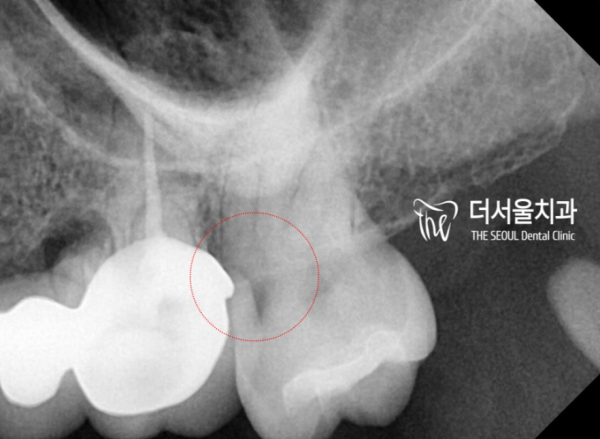

이 환자분역시, 초기에는 잘 모르시다가

통증이 있으셔서 저희 태평역 더서울치과를 찾아주셨고

엑스레이를 촬영한 결과 인접면에 충치가 발견된 사례입니다.

육안으로 다시 보면, 역시 충치가 잘 보이지 않습니다.

이 인접면에 충치가 있다는 것을 알기가 어렵고, 환자분의 통증으로 인해

확인하게 된 것이죠.

방사선 사진으로는 충치의 범위, 위치등을 확인할 수 있습니다.

신경과 가까이 있는 위치이기 때문에 신경치료를 할 수 밖에 없습니다.